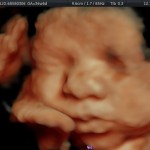

- El Doppler de las arterias uterinas maternas y determinación de riesgo para pre eclampsia severa.